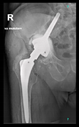

The guiding wire was inserted and controlled with fluoroscopy flashes (Figure 4). The drilling and reaming were carried out in accordance with the recommendations:

Figure 4.

The biocompatible aiming device after insertion of the guiding wire.

The radiological examination allowed us to verify the close bone-to-implant contact and the unchanged position of the implant during follow-up.

In all the cases operated with the above-described targeting procedure, the stems of the cups remained between the cortical bone surfaces without perforation of the linea terminalis, as shown by postoperative radiographs. There were no complicated surgical situations. In 16 cases, the wound healings were uneventful, and the hips were able to bear weight again after postoperative rehabilitation.